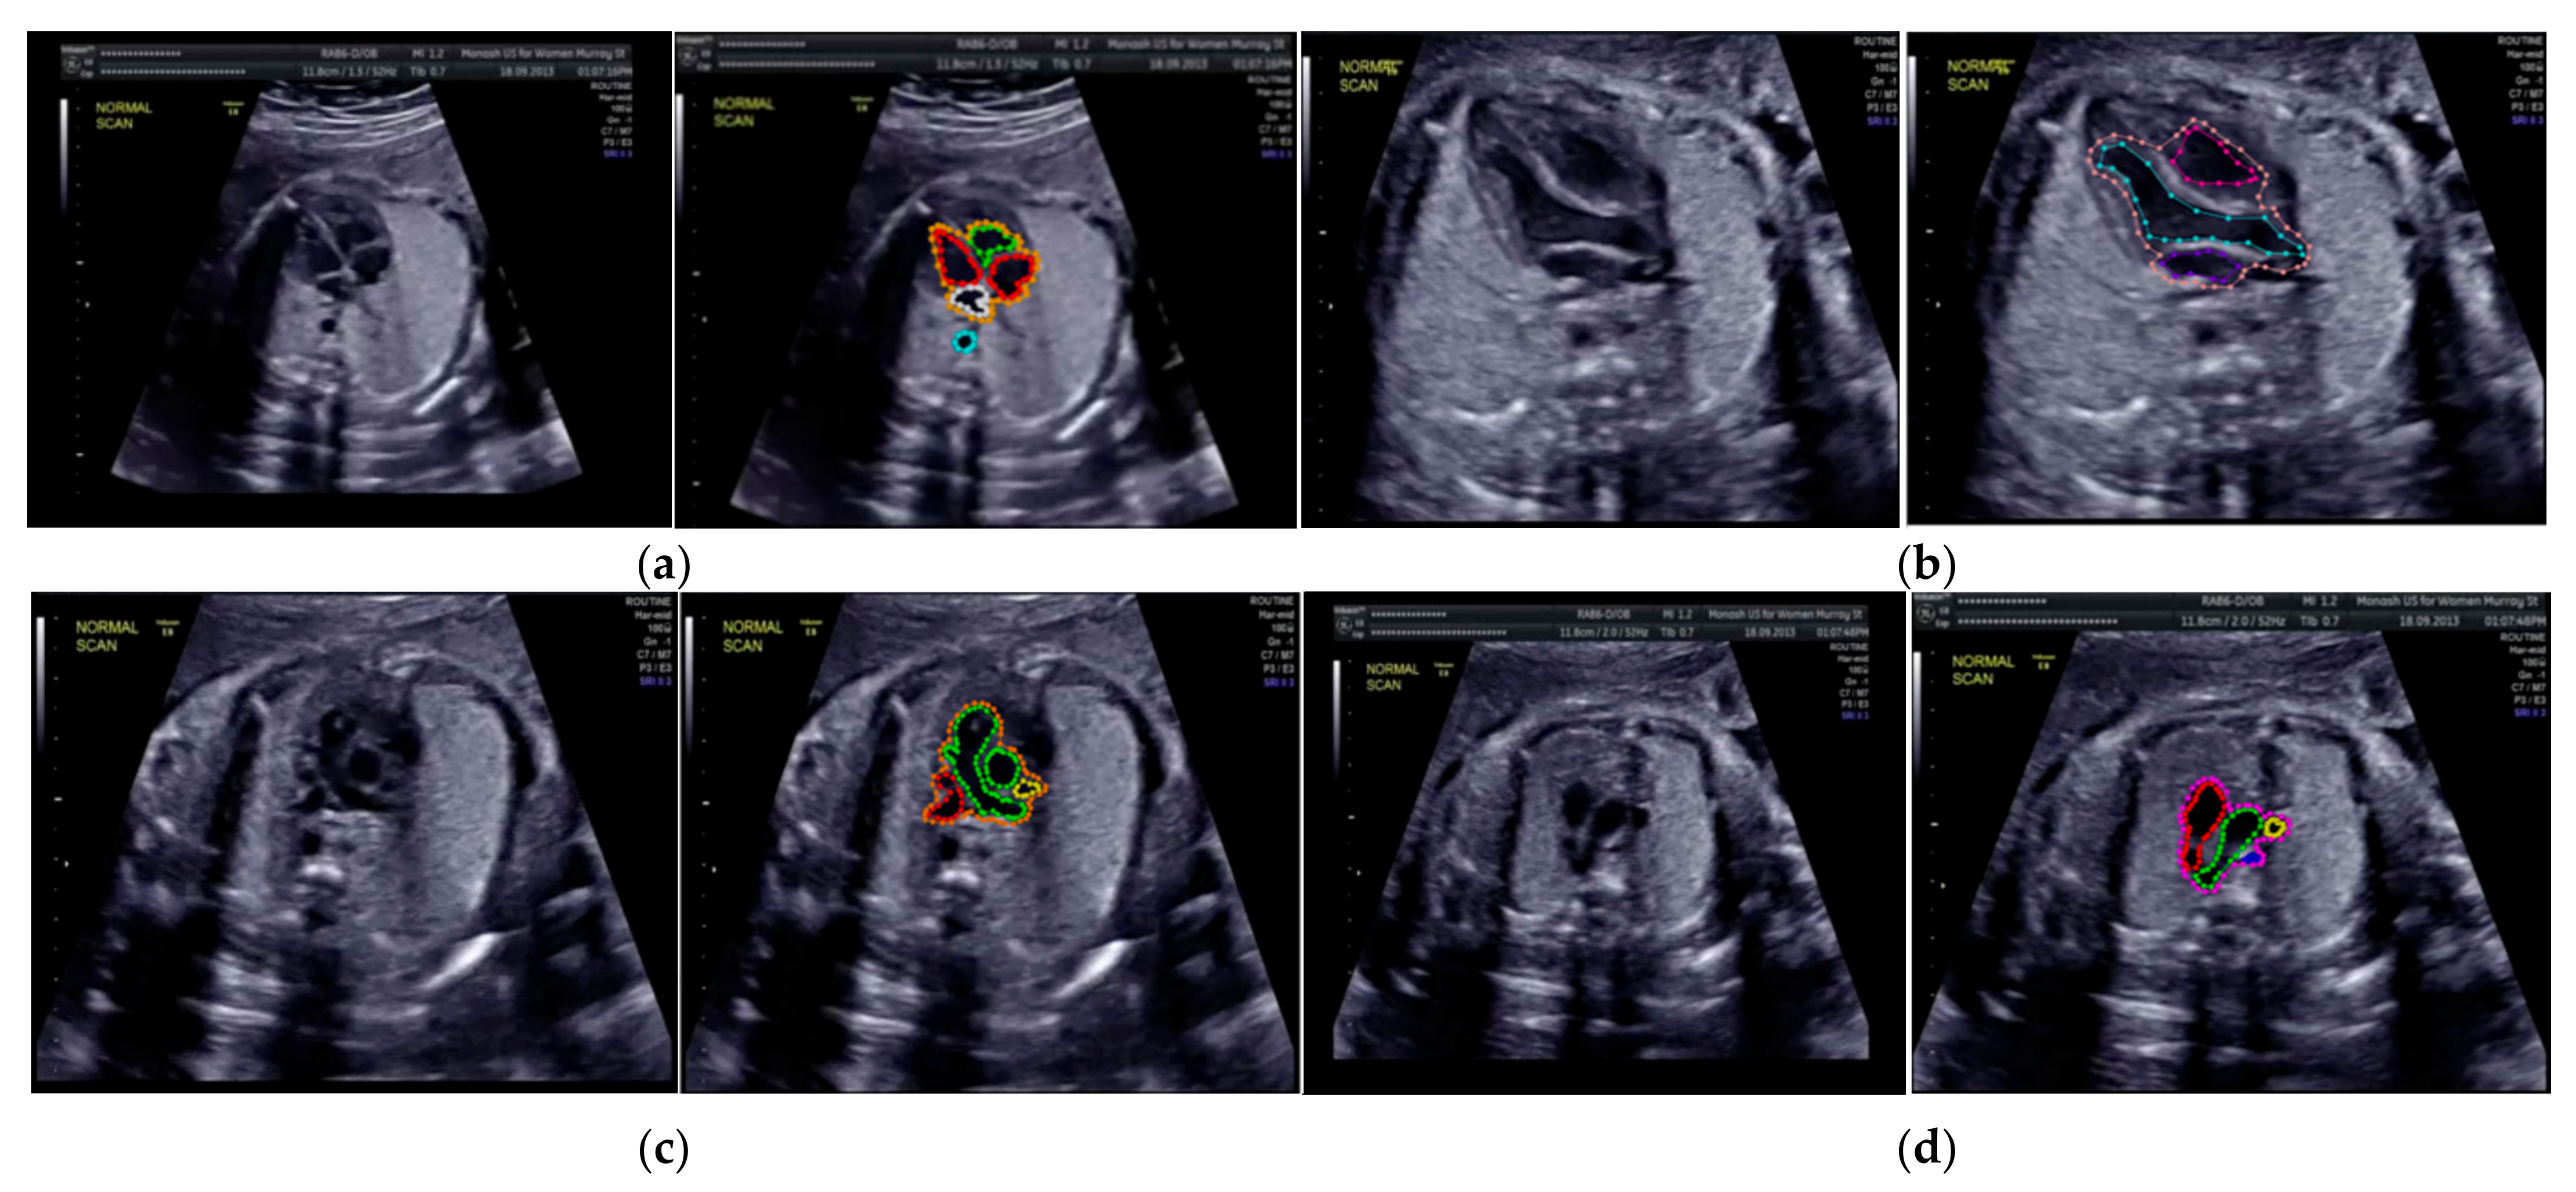

The sample image of heart defect segmentation and detection is depicted in Figure 12. In the 18–21 weeks of pregnancy, the fetal heart has size around 24 mm [23], thus the hole (defect) size in the heart septum will have a size <24 mm. At this stage of development, therefore, it remains difficult to visualize with precision the details of cardiac anatomy as seen during fetal echocardiography. By using our proposed model, it can be segmented and detected with IoU and DCS about 59% and 69%, respectively, in intra-patient, and about 47% IoU and 57% DCS in inter-patient scenarios. This means our model has the ability to segment and detect until a 50% overlap with the ground truth.

Figure 12.

Sample image result of CHDs detection with 4CH view. The white arrow indicates the defect, whereas red and blue colors are the defect position in the heart septum.

This study determined the mAP value for each defect condition (ASD, VSD, and AVSD) in addition to the IoU and DCS values. A high mAP value indicated that the defect prediction from the model was similar to the ground truth generated by the maternal–fetal consultant. Table 6 shows the object detection results with mAP performance; the highest mAP value (98.30%) was obtained from the intra-patient data; however, the mAP decreased to 82.42% in the inter-patient data. CNN-based instance segmentation works using a simple linear iterative clustering algorithm, which takes an image as input and outputs its division into super-pixels. The proposed model measures the overlap between the annotated input and predicted target, but it does not label all the image pixels, as it segments only the RoI. Therefore, if the input image is new (from inter-patient), the detection performance will decrease, but its performance still satisfactory due to the reduction only 16% with the mAP value over 80%.

We also conducted heart chamber segmentation and detection in 4CH view with abnormal anatomy image. The fetal heart chamber prediction with the proposed model is presented in Figure 13. This experimental result differed from the IoU and DCS performance in Figure 11, as the fetal heart images are taken from the patients with CHDs. The experiment was conducted based on intra- and inter-patient data. The RoI was a segment of four object classes, namely, LA, LV, RA, and RV. With the use of the Mask-RCNN model, all classes can be segmented and classified in the three conditions. Overall performances show that intra-patient data allowed better IoU and DCS performance compared with inter-patient data.

Figure 13.

As shown in Figure 13a,d, the proposed model produced satisfactory results, with a large overlap between the ground truth and the predicted image. All IoU values exceeded the baseline of 0.5, which is the gold standard value for ensuring that all processes can be run with good performance. The IoU and DCS performances with the intra-patient data were better than those with the inter-patient data, with scores of above 66.37% and 79.60%, respectively. The performance with the inter-patient data was poorer than that with the intra-patient data. Due to the inherent differences in appearance across different imaging modalities, it is challenging to construct accurate image similarity measures. As the underlying anatomical components vary between patients, inter-patient registration might be difficult. In future work, the detection performance for the inter-patient scenario should be enhanced. The image sample for the heart chamber with a heart defect can be seen in Figure 14 with the defect position marked in red and blue. In this detection process, the defect can be small or large, depending on its severity. However, in this study, the defect size parameter was not taken into account; for further research, it will be very important to diagnose the severity of the condition.

Figure 14.

The sample result of wall-chamber segmentation with 4 CH view in ASD, VSD, and AVSD condition based on abnormal anatomy structure.